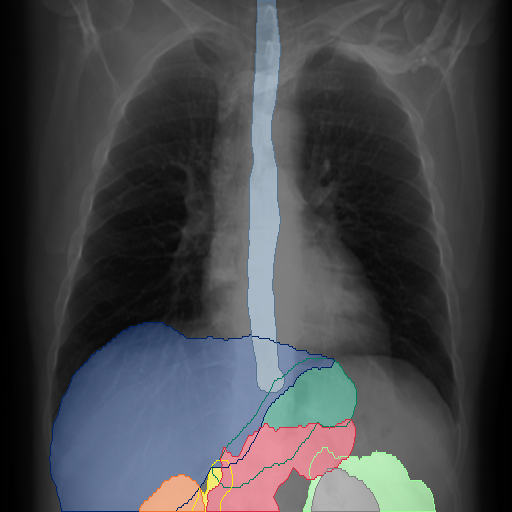

We show qualitative results for frontal projections in Fig. 2. We show a subset of classes belonging to the supercategories lungs, vascular systems, bones, and abdomen/digestive system. The predictions show minor deviations at the boundaries of the individual classes of the respiratory and vasculature system, while some inaccuracies become visible in the abdominal area. The qualitative results for the lateral projections are displayed in Fig. 2. Akin to the frontal view, the predictions show smoother borders but align with the ground truth. Apart from this, the segmentations provide matching insights on the thoracic anatomy with a slight deviation from the ground truth for both frontal and lateral views.

We display qualitative results in Fig. 3. The annotators tend to be content with most annotations. There are edits at the extensions of the esophagus, trachea, and aorta and corrections of the lower ribs. There is little consensus for classes in the abdominal area, such as the stomach, as seen on the right of Fig. 3 . In contrast, the annotators often align for bone classes.